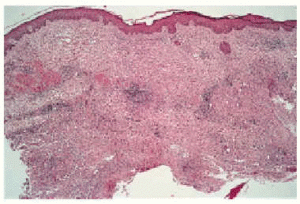

Hemos revisado desde el año 1995 hasta la actualidad las historias clínicas de pacientes con sospecha de infección cutánea por M. chelonae. Sólo los casos con cultivo positivo para este microorganismo fueron incluidos en esta revisión (tabla 1). Se trata de 6 pa-cientes, todas ellas mujeres, con edades comprendidas entre los 16 y 62 años (edad media: 24 años). Referían la aparición de 1 a 4 meses antes de la consulta de una o más lesiones de diferente morfología (pápulas, pústulas o nódulos) que en alguna ocasión se rompían y drenaban un material purulento (fig. 1). Las lesiones estaban localizadas de forma predominante en extremidades inferiores (fig. 2). Todas eran pacientes previamente sanas y no relataban un claro antecedente traumático, excepto la paciente número 6 que refirió el antecedente previo de una liposucción (fig. 3). Ninguna tenía fiebre, dolor o síntomas de enfermedad sistémica. Todas habían realizado tratamiento previo con cloxacilina sin respuesta. Con la exploración presentaban lesiones inflamatorias que se describen en la tabla 1. La mayoría eran lesiones nodulares de localización preferente en extremidades inferiores. El estudio anatomopatológico mostraba densos infiltrados inflamatorios de carácter agudo o crónico y abscesos o lesiones granulomatosas, sin obser- varse focos de necrosis caseosa (fig. 4). En ningún caso se encontraron bacilos ácido-alcohol resistentes en el interior de los granulomas mediante la tinción de Ziehl-Neelsen. En todos los casos se aisló una micobacteria de crecimiento rápido, que posteriormente fue tipificada como M. chelonae en medios de cultivo Coletsos y Lowenstein y en medio BACTEC MGIT 960, medio líquido, con sistema radiométrico para detectar el crecimiento. Las pruebas complementarias realizadas incluyeron un sistemático de sangre, bioquímica sanguínea, sistemático de orina, proteinograma, cuantificación de inmunoglobulinas, serología virus de la inmunodeficiencia humana (VIH), prueba de Mantoux y radiografía de tórax, con resultados normales o negativos. En todas las pacientes se instauró tratamiento con un régimen de antibióticos orales que incluía claritromicina en 5 de ellas, con buenos resultados. Excepto en una paciente que no acudió a revisión, en todas las demás no se encontraron lesiones nuevas y persistían sólo lesiones residuales.

Fig. 4.--Reacción inflamatoria granulomatosa confluente, con fenómenos de abscesificación en dermis profunda (hematoxilina-eosina, 40x.)